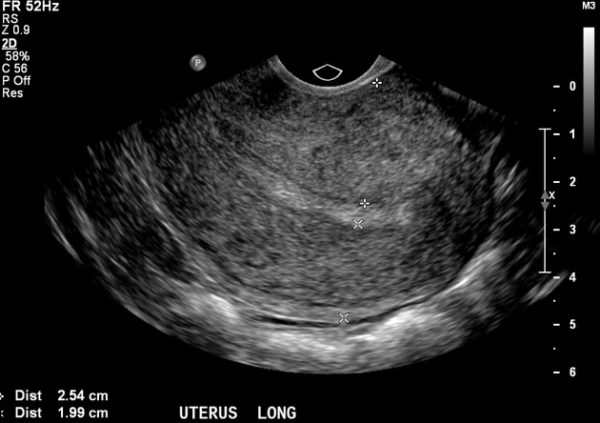

- Форму заболевания можно выявить и с помощью ультразвукового исследования.

Диффузный аденомиоз — это когда нет четких очагов, но присутствуют структурные изменения мышечной ткани. Узловой или очаговый — это когда есть конкретные места формирования узелков, которые очень часто во время УЗИ-диагностики могут путать с миомой матки.